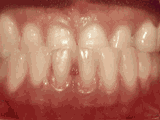

Crowded dentition, lack of anterior teeth occlusion, asymmetrical midline of upper and lower teeth, narrow dental arch, and ectopic eruption of the upper canines. After professional assessment without any tooth extractions, the result of orthodontic treatment is as follows: